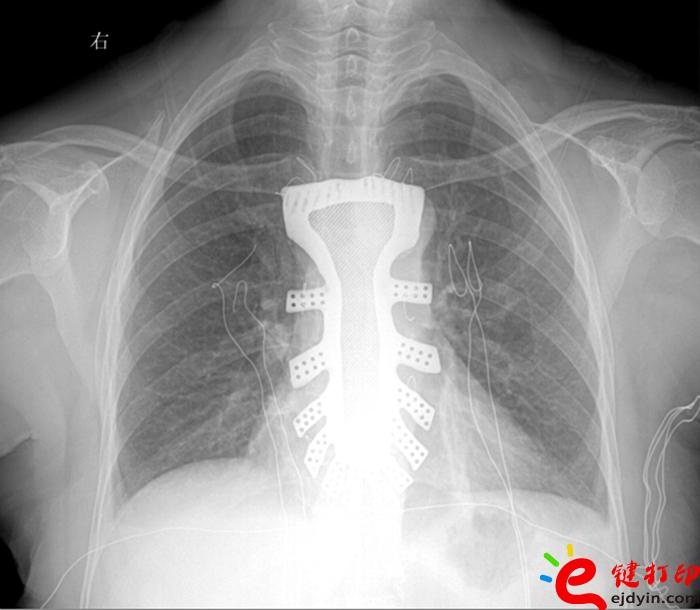

據王小平教授介紹,唐都醫院3D打印小組經過精密計算患者胸骨的大小、形狀等,充分研究討論,歷時一周,為患者設計出了手術使用的3D胸骨模型,并與西北工業大學凝固技術國家重點實驗室合作,為患者打印出了1:1鈦合金胸骨模型。隨后,又對該模型進行了一系列嚴密的醫學處理。

“手術歷時2.5小時,對患者的胸骨進行了整體切除,置換了鈦合金胸骨,目前患者恢復良好,未發現任何并發癥。”王小平教授稱,根據專業機構檢索,該手術是世界首例針對胸骨腫瘤疾病,將3D打印的可植入性鈦合金胸骨植入人體,實現病變胸骨的整體置換的手術。該手術的成功意味著未來將會為更多的胸骨腫瘤患者帶來福音。